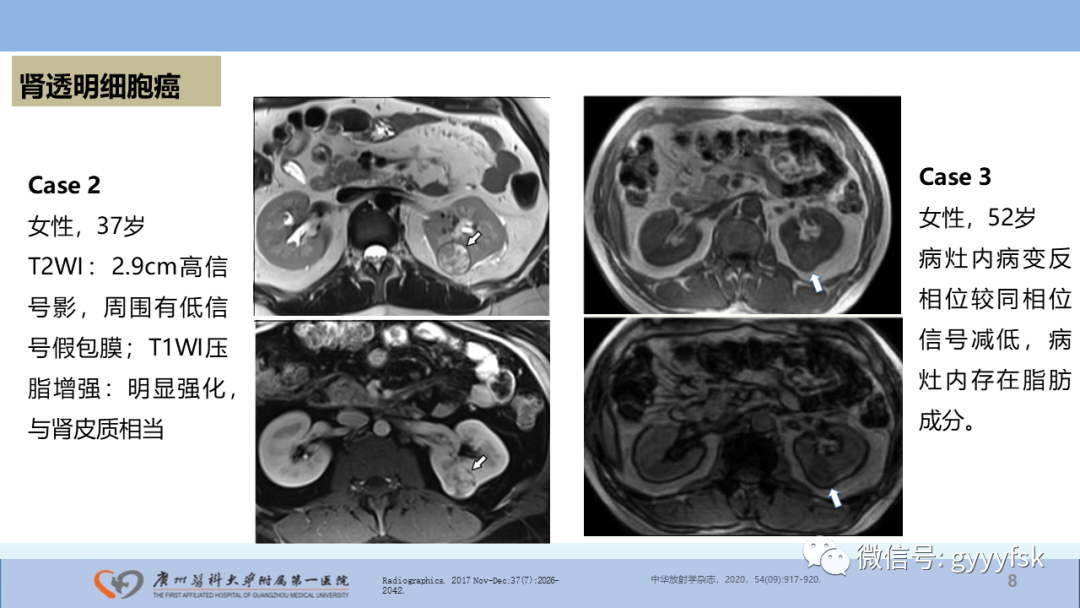

【PPT】肾癌相关影像诊断的文献汇报-8

【PPT】肾癌相关影像诊断的文献汇报-9